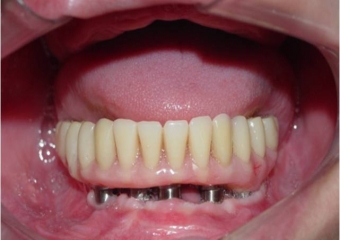

Próteses fixas em resina superior e inferior sobre implantes